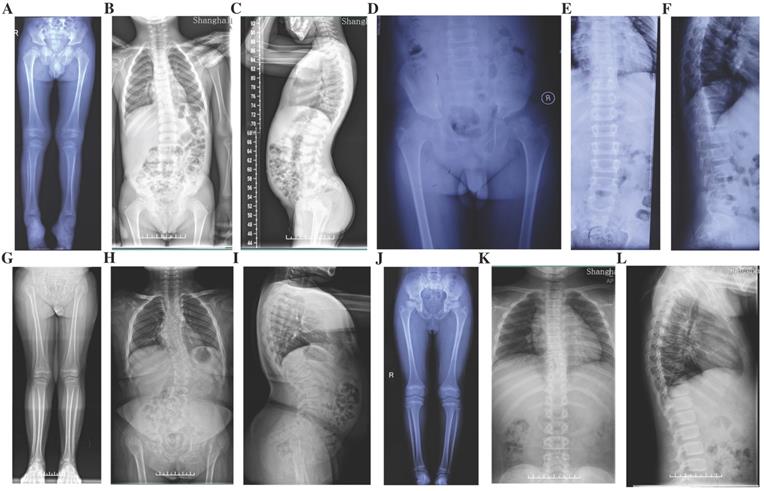

Figure 3

Radiographs of the probands with SEDC. A-C: Full-length X-rays of both lower extremities (A) and spine radiographs (B, C) of the proband in Family 1. Flattening of the acetabular roof, small capital femoral epiphyses, enlarged distal femur metaphyses and ovoid vertebral bodies were displayed. D-F: X-rays of pelvis (D) and spine (E, F) of the proband in Family 2. Partial collapse and uneven density of bilateral femoral heads, flattening of the acetabular roof, shortening of the femoral neck and platyspondyly were shown. G-I: Full-length X-rays of both lower extremities (G) and spine radiographs (H, I) of the proband in Family 3. Small iliac bones, horizontal acetabular roof, coxa vara, very short femoral necks, small and fragmented ossification of capital femoral epiphyses, enlarged distal femur metaphyses, severe scoliosis and moderate platyspondyly were demonstrated. J-L: Full-length X-rays of both lower extremities (J) and spine radiographs (K, L) of the proband in Family 4. Flattening of the acetabular roof, compressed femoral head, shortening of the femoral neck and base of the ilium, distinctly flared metaphyses of femurs and slight platyspondyly were shown.

Four probands from four non-consanguineous families had same initial symptoms of groin pain, limitation in hip mobility and abnomal gait from their 4 to 7 years (Fig. 2). These symtoms increased with age. When they came to our clinic, they were in early adolescence, and with short heights which was at least lower than -2 SD (<-2SD) compared with the average height of healthy Chinese adolescents at the same age (Table 1). Other joints, including knees, elbows, ankles and interphalangeal joints, showed no abnormalities. The hearing, vision, and intellectual development were normal in probands of Family 1 and 2, but in Family 3 and 4, the probands had myopia. X-rays of pelvis, both lower extremities and spines showed flattening of the acetabular roof, small capital femoral epiphyses or partial collapse of bilateral femoral heads, shortening of the femoral neck and base of the ilium, enlarged distal femur metaphyses, coxa vara, scoliosis and platyspondyly (Fig. 3). The parents had no similar signs or symtoms in Family 1, 2 and 3. In Family 4, the father (Ⅰ-1) and brother (Ⅱ-1) of the proband were normal, but the 46-year old mother of the proband (Ⅰ-2) was 141.4-cm tall (<-3SD). Pain in bilateral hip and knee joints appeared at her age of 20, and she had myopia and cataract. X-rays demonstrated rough articular surface, narrowing joint spaces, sclerotic edges of both acetabulums, concave on the upper and lower margin of multiple vertebral bodies.